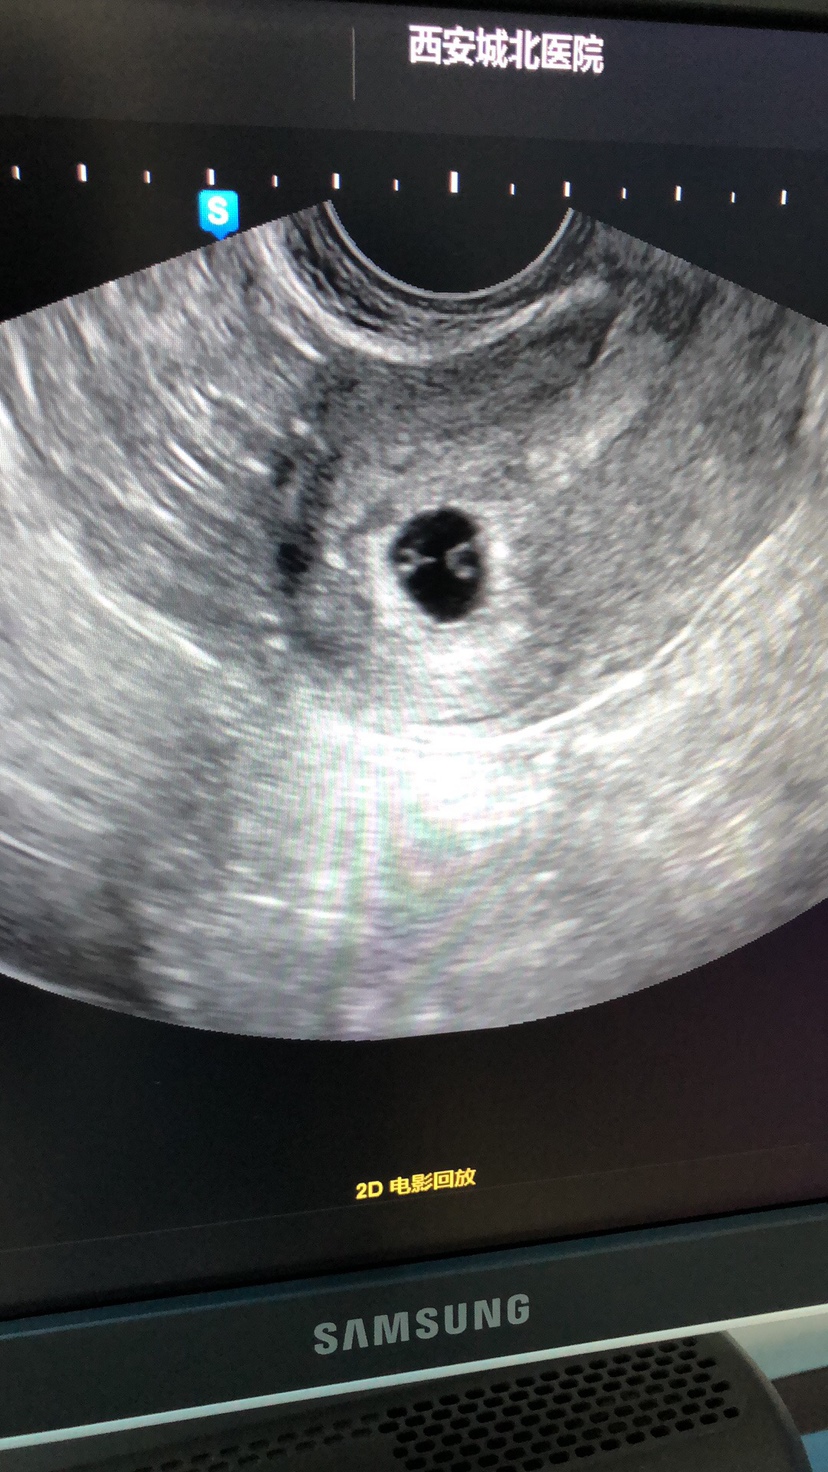

孕7周+1天

璐[帖主]:医生说像是,说左边的有点小,也许长长就被吸收了,让我下周复查!